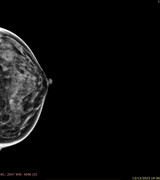

Dottor Catania,

secondo lei in questa mammografia di un anno fa erano presenti microcalcificazioni? Ingrandendo mi sembra di vedere in alto dei puntini...ma mi sa che li vedo perché li voglio vedere.. nella speranza che mi dicano che già c'erano e che non devo rifare tra 6 mesi un'altra mammografia...

Grazie

Ciarlina78

intendo questi puntini che vedo...